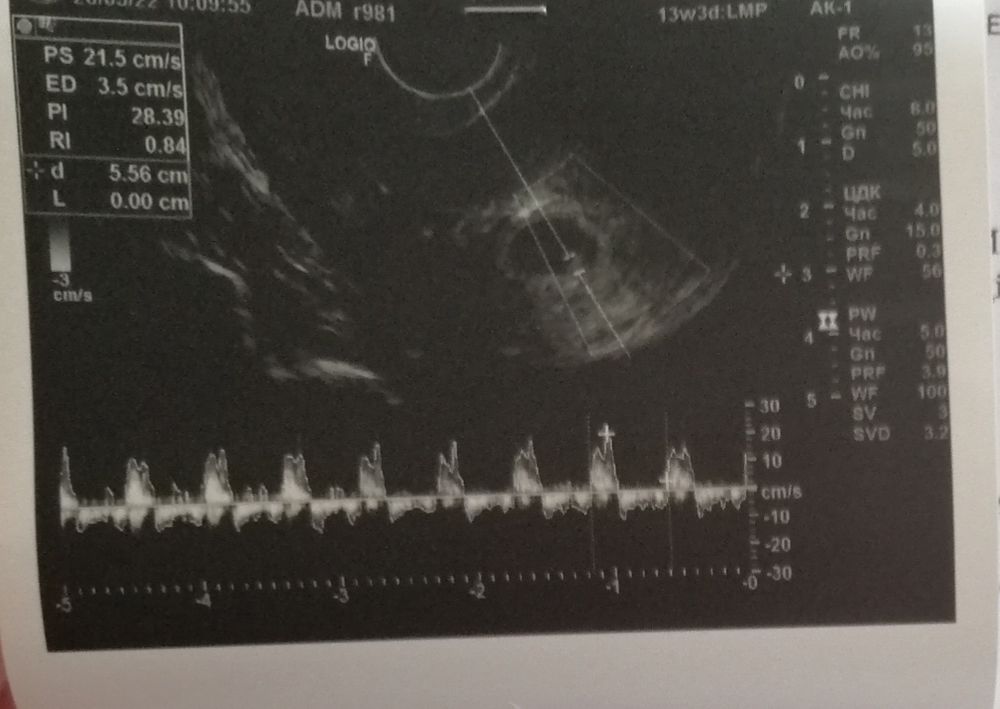

Всем доброго дня. Спасибо девочкам, кто вчера меня встряхнул и сказал бежать в больницу. Начались выделения(коричневатые, но не много) , вчера никак не могла вызвать скорую, нужно было доехать утром до работы, передать ключи. После этого ланью поскакала в ЖК. Так вот, после осмотра направили меня на дневной стационар. Перед этим сделали узи. Мне кажется я давно так не боялась (вдруг сказали бы что все...)

Но нет! Врач сказала, отслойки нет, пульсацию видит, скорей всего сердечко, но пока не понятно, маленькие мы ещё. Сегодня и в последующие дни:дюфастон 3р в день, витамины, покой, дротоверин в случае болей в животе. Завтра куча анализов, и по ним возможна корекция лечения.